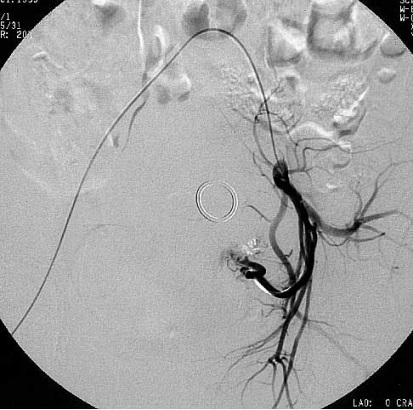

子宫动脉栓塞手术示意图

左子宫动脉栓塞术前肌瘤血供丰